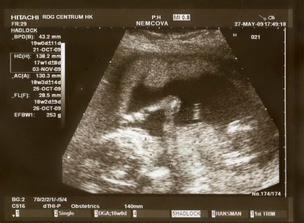

Nová naděje. Bohužel to bylo opět stejné, jako již dvakrát předtím. Třetí revize, třetí ztráta naděje. Jsem po laparoskopii a hysteroskopii a čekáme na výsledky imunologie v Plzni. Pak se uvidí co dál. V únoru 2009 nám v Sanusu doporučili ještě dva měsíce domácího snažení. Tak jsme se snažili a nyní napjatě sledujeme čárku. HCG nám krásně stoupá, 20. den po ovulaci je 2066. Máme 1. fotku dutinky. Přes nejrůznější potíže a patnáctidenní hospitalizaci nám miminko krásně roste. 22. dubna konečně po čtrnácti dnech ukázalo nosánek, máme nosní kůstku, NT je 2,0. Máme vše, co máme mít a rodiče se dnes poprvé společně dívali na ultrazvuk. Viděli mě i 4D, to koukali. Odnesli si video a teď na něj pořád koukají. Další kontrola náš čeká 5. května, opět ultrazvuk, triple testy a poradna. Trošku změna situace, mamka se mnou leží od 27. dubna v nemocnici, ale já ji dělám radost, rostu, 16.6. už vážím 360 gramů a od 5.6. ji kopu a ona o tom ví. Od 10. 6. se nám začal malinko měnit nález až jsme museli 10. 7., gr. h. 24+2 na cerclage, potom jsme měli zánět ledvin a astmatický záchvat. Pořád mamce tvrdlo břicho, tak se bez infuzí neobejde. 18. 7. se ještě objevilo krvácení, ale nebylo to nic závažného, byli jsme na ultrazvuku a vážím 908 gramů. V pátek 24.7. se to zlepšilo a kapeme na nejnižší rychlost, hurá. Mamka zatím nesmí chodit, má to slíbeno na 2. září. Kapeme sice na nejvyšší rychlosti, ale na ultrazvuku 4.8. mám odhad 1280 gramů. Dne 18.8. jsme byli na ultrazvuku a mám odhad 1750 gramů, mám trochu víc plodové vody a tak si tam plavu jako v bazénku. Dne 28.8. jsme byli s mamkou zase na ultrazvuku, vážím už 1950 gramů, mám udělaný krásný 3D fotečky, vody už nemám tolik moc, tak je mamka ráda. Jen se nám zase zkrátil čípek, už mě tam drží jen steh a 13 mm, ale držím mamce pěstičky, aby jsme vydrželi. No a taky si musím zvykat, mamka totiž má už dovoleno chodit na wc, a já jsem byl zvyklej, že pořád leží. Je sice z toho unavená, ale šťastná. Já jsem jí ještě udělal radost, že jsem se přetočil hlavičkou dolů. Dne 1.9. se mi konečně podařilo zbavit se té nitě, co tam mamka měla. Všichni jsou překvapení, jak se to mohlo stát, ale steh je pryč. Dne 10. 9. jsme s mamkou byli zase na ultrazvuku, vážím 2368 gramů (33+1). Hrdlo máme sice jen 9 mm, ale já se tam ještě udržím! Plodové vody mám už akorát, mamce klesly jaterní testy, žlučové kyseliny jsou v normě, tak má radost. Tak dnes 17. 9. jsem se byl zase vážit, mám 2517 gramů. Hrdlo má mamka jen 6,7 mm s obrovitým funnelingem, ale pořád drží. Denně mi točí monitory, mám je vzorné a pořád nemůžu přijít na to, jak ty sondy odkopnout. 26.9. pustil pan doktor mamku na propustku, byla poprvé 12 hodin mimo nemocnici, byli jsme na zahradě, grilovali jsme a já jsem babičce, dědečkovi a strejdovi předváděl, jak umím krásně kopat. Mamka byla moc šťastná. Večer se vrátila do nemocnice, dala si po 23. hodině sprchu a když usínala, tak jsem ji hodně překvapil, vypustil jsem svůj bazén. A tak se nešlo spinkat, ale na porodní sál. Šlo to pěkně a přesně ve 4.00 hodin jsem se narodil za skvělé asistence mého tatínka, který mamince na sále moc pomáhal. Vážím 2740 gramů a měřím 50 cm. Dosáhl jsem gestačního stáří 35+4. Rodiče a velká spousta lidí kolem ze mě mají velikánskou radost. Trošku jsem odmítal v inkubátoru dýchat, tak mě 1 den pomáhal CPAP. Večer mi ho vzali a teď už se snažím sám. mamka za mnou chodí a já jsem rád, když ji vídím. Dnes jsem na ni poprvé otevřel očička, snažím se papat, dnes už ze stříkačky. Tatínek je ze mě unešenej a já jsem rád, když mě přijde pohladit a vyfotit.